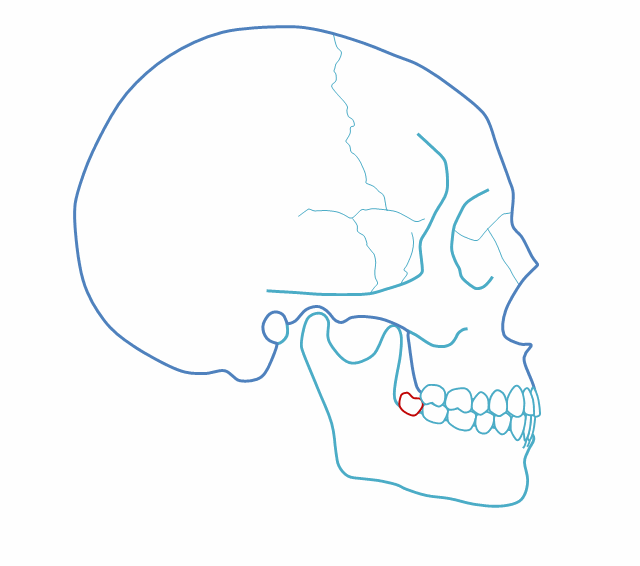

第二,完全埋在骨頭里可以不拔?

完全埋在牙槽骨里的下頜智齒,它本身倒是不出問(wèn)題。但是這些近中或水平阻生的智齒,會(huì)推擠下頜第二磨牙,導(dǎo)致第二磨牙伸長(zhǎng):

然后,第二磨牙造成咬合干擾、早接觸,前牙開(kāi) 牙合…………

所以,這種智齒也還是要 拔掉。